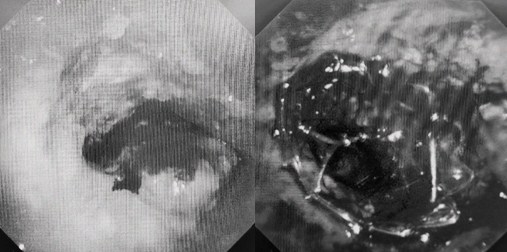

運(yùn)用呼吸介入技術(shù),軟硬鏡結(jié)合快速開通氣道,是患者目前唯一可行的治療方案,手術(shù)刻不容緩!但存在麻醉后氣道完全塌陷閉合、大出血、窒息等巨大風(fēng)險(xiǎn)?;颊叽饲敖舆B轉(zhuǎn)診3家醫(yī)院,均建議保守支持治療或轉(zhuǎn)院。歐陽海峰詳細(xì)了解患者病史,全面評(píng)估影像檢查結(jié)果后,決定盡快進(jìn)行手術(shù),組織醫(yī)護(hù)團(tuán)隊(duì)對(duì)患者進(jìn)行持續(xù)密切監(jiān)測(cè),充分保障其術(shù)前安全。

患者入院第二天,在麻醉手術(shù)中心全力配合下,歐陽海峰帶領(lǐng)呼吸介入團(tuán)隊(duì),歷時(shí)40分鐘快速置入硬質(zhì)支氣管鏡、鏟切腫瘤,并順利植入全覆膜TTS支氣管金屬支架?;颊邭舛贪Y狀即刻緩解,為患者贏得了寶貴的后續(xù)治療機(jī)會(huì)。